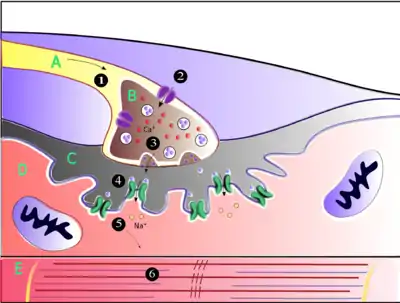

.png.webp)

Muscles require innervation to function—and even just to maintain muscle tone, avoiding atrophy. In the neuromuscular system, nerves from the central nervous system and the peripheral nervous system are linked and work together with muscles.[2] Synaptic transmission at the neuromuscular junction begins when an action potential reaches the presynaptic terminal of a motor neuron, which activates voltage-gated calcium channels to allow calcium ions to enter the neuron. Calcium ions bind to sensor proteins (synaptotagmins) on synaptic vesicles, triggering vesicle fusion with the cell membrane and subsequent neurotransmitter release from the motor neuron into the synaptic cleft. In vertebrates, motor neurons release acetylcholine (ACh), a small molecule neurotransmitter, which diffuses across the synaptic cleft and binds to nicotinic acetylcholine receptors (nAChRs) on the cell membrane of the muscle fiber, also known as the sarcolemma. nAChRs are ionotropic receptors, meaning they serve as ligand-gated ion channels. The binding of ACh to the receptor can depolarize the muscle fiber, causing a cascade that eventually results in muscle contraction.

At the neuromuscular junction presynaptic motor axons terminate 30 nanometers from the cell membrane or sarcolemma of a muscle fiber. The sarcolemma at the junction has invaginations called postjunctional folds, which increase its surface area facing the synaptic cleft.[3] These postjunctional folds form the motor endplate, which is studded with nicotinic acetylcholine receptors (nAChRs) at a density of 10,000 receptors/µm2.[4] The presynaptic axons terminate in bulges called terminal boutons (or presynaptic terminals) that project toward the postjunctional folds of the sarcolemma. In the frog each motor nerve terminal contains about 300,000 vesicles, with an average diameter of 0.05 micrometers. The vesicles contain acetylcholine. Some of these vesicles are gathered into groups of fifty, positioned at active zones close to the nerve membrane. Active zones are about 1 micrometer apart. The 30 nanometer cleft between nerve ending and endplate contains a meshwork of acetylcholinesterase (AChE) at a density of 2,600 enzyme molecules/µm2, held in place by the structural proteins dystrophin and rapsyn. Also present is the receptor tyrosine kinase protein MuSK, a signaling protein involved in the development of the neuromuscular junction, which is also held in place by rapsyn.[3]

About once every second in a resting junction randomly one of the synaptic vesicles fuses with the presynaptic neuron's cell membrane in a process mediated by SNARE proteins. Fusion results in the emptying of the vesicle's contents of 7000–10,000 acetylcholine molecules into the synaptic cleft, a process known as exocytosis.[5] Consequently, exocytosis releases acetylcholine in packets that are called quanta. The acetylcholine quantum diffuses through the acetylcholinesterase meshwork, where the high local transmitter concentration occupies all of the binding sites on the enzyme in its path. The acetylcholine that reaches the endplate activates ~2,000 acetylcholine receptors, opening their ion channels which permits sodium ions to move into the endplate producing a depolarization of ~0.5 mV known as a miniature endplate potential (MEPP). By the time the acetylcholine is released from the receptors the acetylcholinesterase has destroyed its bound ACh, which takes about ~0.16 ms, and hence is available to destroy the ACh released from the receptors.

When the motor nerve is stimulated there is a delay of only 0.5 to 0.8 msec between the arrival of the nerve impulse in the motor nerve terminals and the first response of the endplate [6] The arrival of the motor nerve action potential at the presynaptic neuron terminal opens voltage-dependent calcium channels and Ca2+ ions flow from the extracellular fluid into the presynaptic neuron's cytosol. This influx of Ca2+ causes several hundred neurotransmitter-containing vesicles to fuse with the presynaptic neuron's cell membrane through SNARE proteins to release their acetylcholine quanta by exocytosis. The endplate depolarization by the released acetylcholine is called an endplate potential (EPP). The EPP is accomplished when ACh binds the nicotinic acetylcholine receptors (nAChR) at the motor end plate, and causes an influx of sodium ions. This influx of sodium ions generates the EPP (depolarization), and triggers an action potential that travels along the sarcolemma and into the muscle fiber via the T-tubules (transverse tubules) by means of voltage-gated sodium channels.[7] The conduction of action potentials along the T-tubules stimulates the opening of voltage-gated Ca2+ channels which are mechanically coupled to Ca2+ release channels in the sarcoplasmic reticulum.[8] The Ca2+ then diffuses out of the sarcoplasmic reticulum to the myofibrils so it can stimulate contraction. The endplate potential is thus responsible for setting up an action potential in the muscle fiber which triggers muscle contraction. The transmission from nerve to muscle is so rapid because each quantum of acetylcholine reaches the endplate in millimolar concentrations, high enough to combine with a receptor with a low affinity, which then swiftly releases the bound transmitter.

Acetylcholine is a neurotransmitter synthesized from dietary choline and acetyl-CoA (ACoA), and is involved in the stimulation of muscle tissue in vertebrates as well as in some invertebrate animals. In vertebrates, the acetylcholine receptor subtype that is found at the neuromuscular junction of skeletal muscles is the nicotinic acetylcholine receptor (nAChR), which is a ligand-gated ion channel. Each subunit of this receptor has a characteristic "cys-loop", which is composed of a cysteine residue followed by 13 amino acid residues and another cysteine residue. The two cysteine residues form a disulfide linkage which results in the "cys-loop" receptor that is capable of binding acetylcholine and other ligands. These cys-loop receptors are found only in eukaryotes, but prokaryotes possess ACh receptors with similar properties.[4] Not all species use a cholinergic neuromuscular junction; e.g. crayfish and fruit flies have a glutamatergic neuromuscular junction.[3]

AChRs at the skeletal neuromuscular junction form heteropentamers composed of two α, one β, one ɛ, and one δ subunits.[9] When a single ACh ligand binds to one of the α subunits of the ACh receptor it induces a conformational change at the interface with the second AChR α subunit. This conformational change results in the increased affinity of the second α subunit for a second ACh ligand. AChRs, therefore, exhibit a sigmoidal dissociation curve due to this cooperative binding.[4] The presence of the inactive, intermediate receptor structure with a single-bound ligand keeps ACh in the synapse that might otherwise be lost by cholinesterase hydrolysis or diffusion. The persistence of these ACh ligands in the synapse can cause a prolonged post-synaptic response.[10]